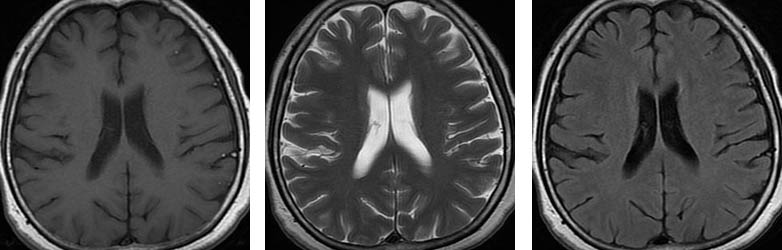

Üç farklı seviyeden aksiyal planda TlAG, T2AG ve FLAIR görüntüler Subaraknoid mesafelerde, özellikle BOS'un hipointens izlendiği TlAG ve FLAIR sekanslarda dağınık milimetrik hiperintens od aklar dikkati çekmektedir.

Pantopaque yağa benzer şekilde kısa T1 ve T2 reIaksasyon sürelerine sahiptir. Bu nedenle Tl ve T2AG'Ierde hiperintens olarak izIenirIer ve özellikle BOS mesafelerinin baskılandığı T1AG ve FLAIR sekanslarında dikkati çekerler.